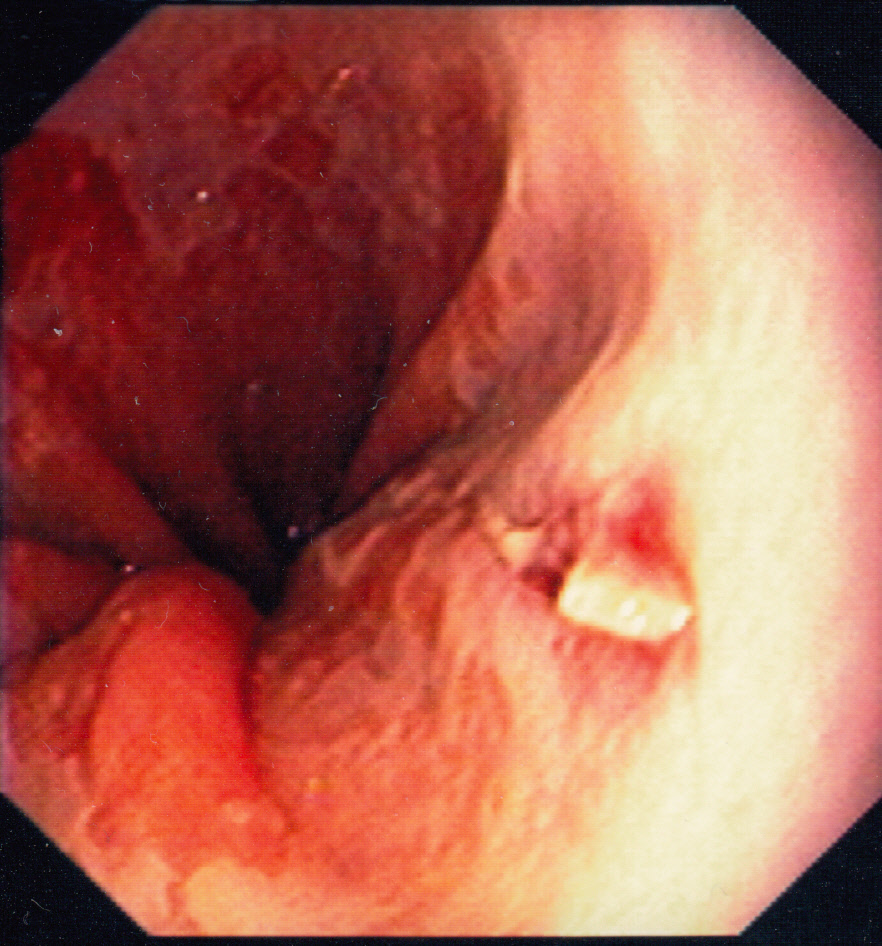

Mallory Weiss-tear

Mallory–Weiss syndrome or gastro-esophageal laceration syndrome refers to bleeding from a laceration in the mucosa at the junction of the stomach and esophagus. This is usually caused by severe vomiting because of alcoholism or bulimia,[1] but can be caused by any conditions which causes violent vomiting and retching such as food poisoning. The syndrome presents with hematemesis. The laceration is sometimes referred to as a Mallory-Weiss tear. (Source: Wikipedia)